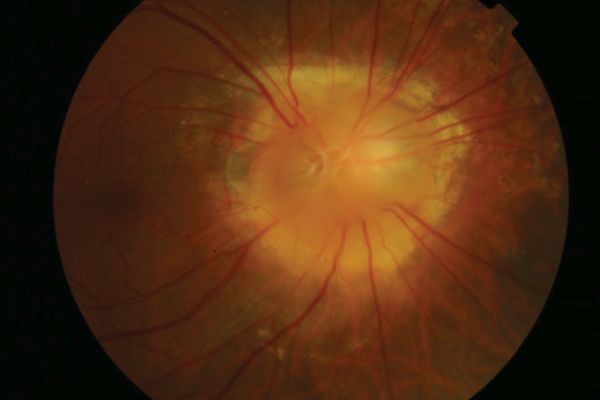

Morning glory anomaly is a rare congenital malformation of the optic nerve.[2] It is named for its resemblance to the morning glory flower.[3] When it is associated with systemic signs and symptoms, it is known as morning glory syndrome.

The optic nerve appears large and funneled.[4] There is a conical excavation of the dysplastic optic disc and the surrounding posterior pole, filled with glial tissue.[3] An increased number of straight retinal vessels arise from the disc margin and peripapillary pigmentation can also been seen.[3] The term “macular capture” is used when the macula is involved in the excavation.[4] Contractions of the optic nerve have also been described and is attributed to the presence of myofibroblasts in the papillae.[3] Due to unilateral involvement in most cases, an afferent pupillary defect can be noted.[3]